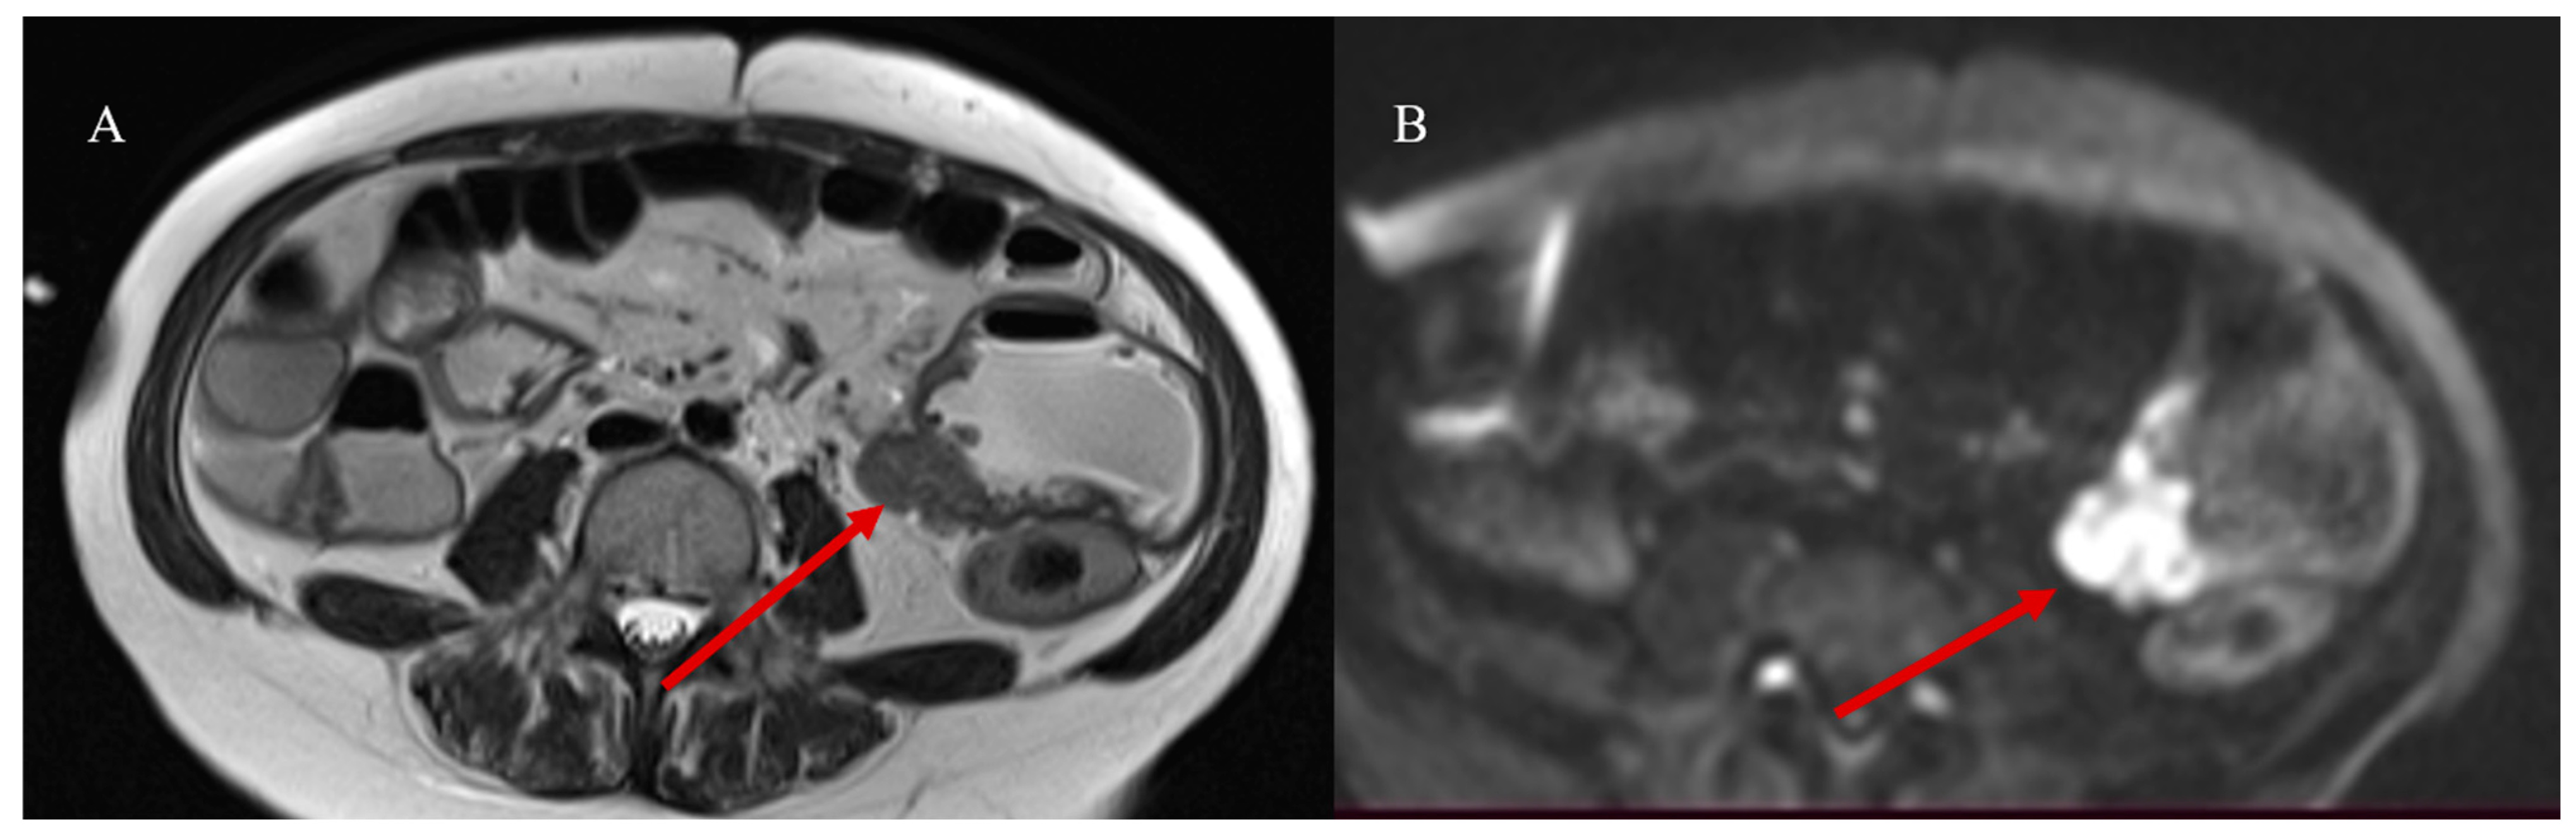

- Masselli, G.; Casciani, E.; Polettini, E.; Laghi, F.; Gualdi, G. Magnetic resonance imaging of small bowel neoplasms. Cancer Imaging 2013, 13, 92–99. [Google Scholar] [CrossRef] [PubMed]

- Pezzella, M.; Brogna, B.; Romano, A.; Torelli, F.; Esposito, G.; Petrillo, M.; Romano, F.; Di Martino, N.; Reginelli, A.; Grassi, R. Detecting a rare composite small bowel lymphoma by Magnetic Resonance Imaging coincidentally: A case report with radiological, surgical and histopathological features. Int. J. Surg. Case Rep. 2018, 46, 50–55. [Google Scholar] [CrossRef]